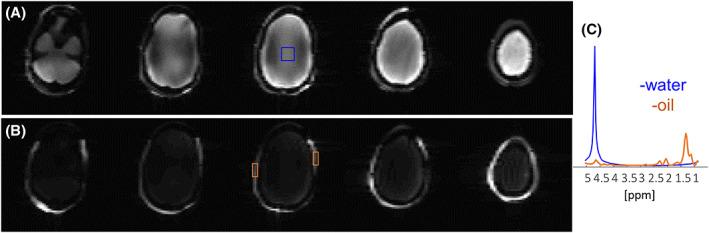

RESULTS

The B and B maps showed distribution similar to that of human brain, with increased B inhomogeneity near the nasal and ear areas and reduced B in the temporal lobe and brain stem regions, as expected in vivo. The metabolites' concentrations were verified by single-voxel spectroscopy, showing an average deviation of 11%. Fast spectroscopic imaging and imaging with fat suppression were demonstrated.

构建了一个具有三个部分(模拟脑、肌肉和颅前脂质)的 3D 人头形状容器。该仿体设计为提供对加热、机械损伤和泄漏的稳定性,便于重新填充。对头的形状和琼脂糖混合物进行了优化,以提供类似于人脑的 B 和 B 分布和 T / T 弛豫值。包括 8 种脑组织模拟代谢物进行波谱分析。对局部波谱、快速波谱成像和脂肪抑制进行了评估。

结果

B 和 B 图谱显示出与人脑相似的分布,在鼻和耳区域附近的 B 不均匀性增加,在颞叶和脑干区域的 B 减少,这与体内预期的情况一致。通过单体素波谱验证了代谢物的浓度,平均偏差为 11%。展示了快速波谱成像和带有脂肪抑制的成像。